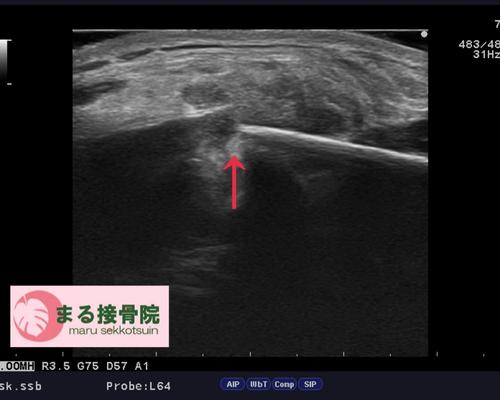

すぐにエコー検査を実施した結果、**「鎖骨骨折」**が確認されました。

鎖骨骨折エコー.JPG

骨折部位の形状から、自然な骨癒合を待つより手術による固定のほうが早期回復につながる可能性が高いと判断。

提携の整形外科にレントゲン検査を依頼し、結果的に手術適応となりました。